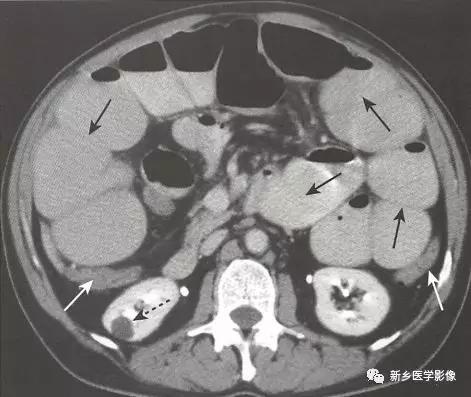

1、病理生理学: 存在一种结肠内部或外部的病变阻塞肠腔。随着时间推移,结肠将从梗阻点逆行扩张,即使梗阻最远端位于乙,状结肠,盲肠也通常在扩张的结肠中直径最大。

大肠正常具有吸收水的功能,所以在梗阻的结肠中很少见到或没有气-液平面。随着时间推移,持续的蠕动波将推动梗阻远端的结肠内容物向前移动至排出。在机械性大肠梗阻中,在直肠中通常很少见到或没有气体影。

梗阻近端结肠扩张。

由于大肠肠襻数目有限,且不互相重叠(如小肠肠襻),所以有时可以通过观察最后含气的结肠肠段来确定梗阻部位。

不论肠梗阻部位在何处,盲肠往往是结肠的扩张最严重的肠段,当盲肠直径达到15cm以上时,须警惕盲肠破裂的风险。

小肠不扩张(除非回盲瓣功能不全)。

因为直肠常常位于梗阻部位以远,所以直肠内包含很少气体或没有气体。

由于大肠具有重新吸收水的功能,大肠内通常没有或很少气-液平面。

只要回盲瓣可以阻止气体逆行进入小肠( 即回盲瓣功能完整),结肠将在回盲瓣和结肠梗阻部位间继续扩张,而小肠不扩张。

但如果结肠内压力过高导致回盲瓣开放(即回盲瓣功能不全),气体将从扩张的大肠逆行进入小肠,就像空气从气球逸出一样。

此时,相对于塌陷的大肠,小肠显示出不成比例的扩张,即可类似机械性小肠梗阻。